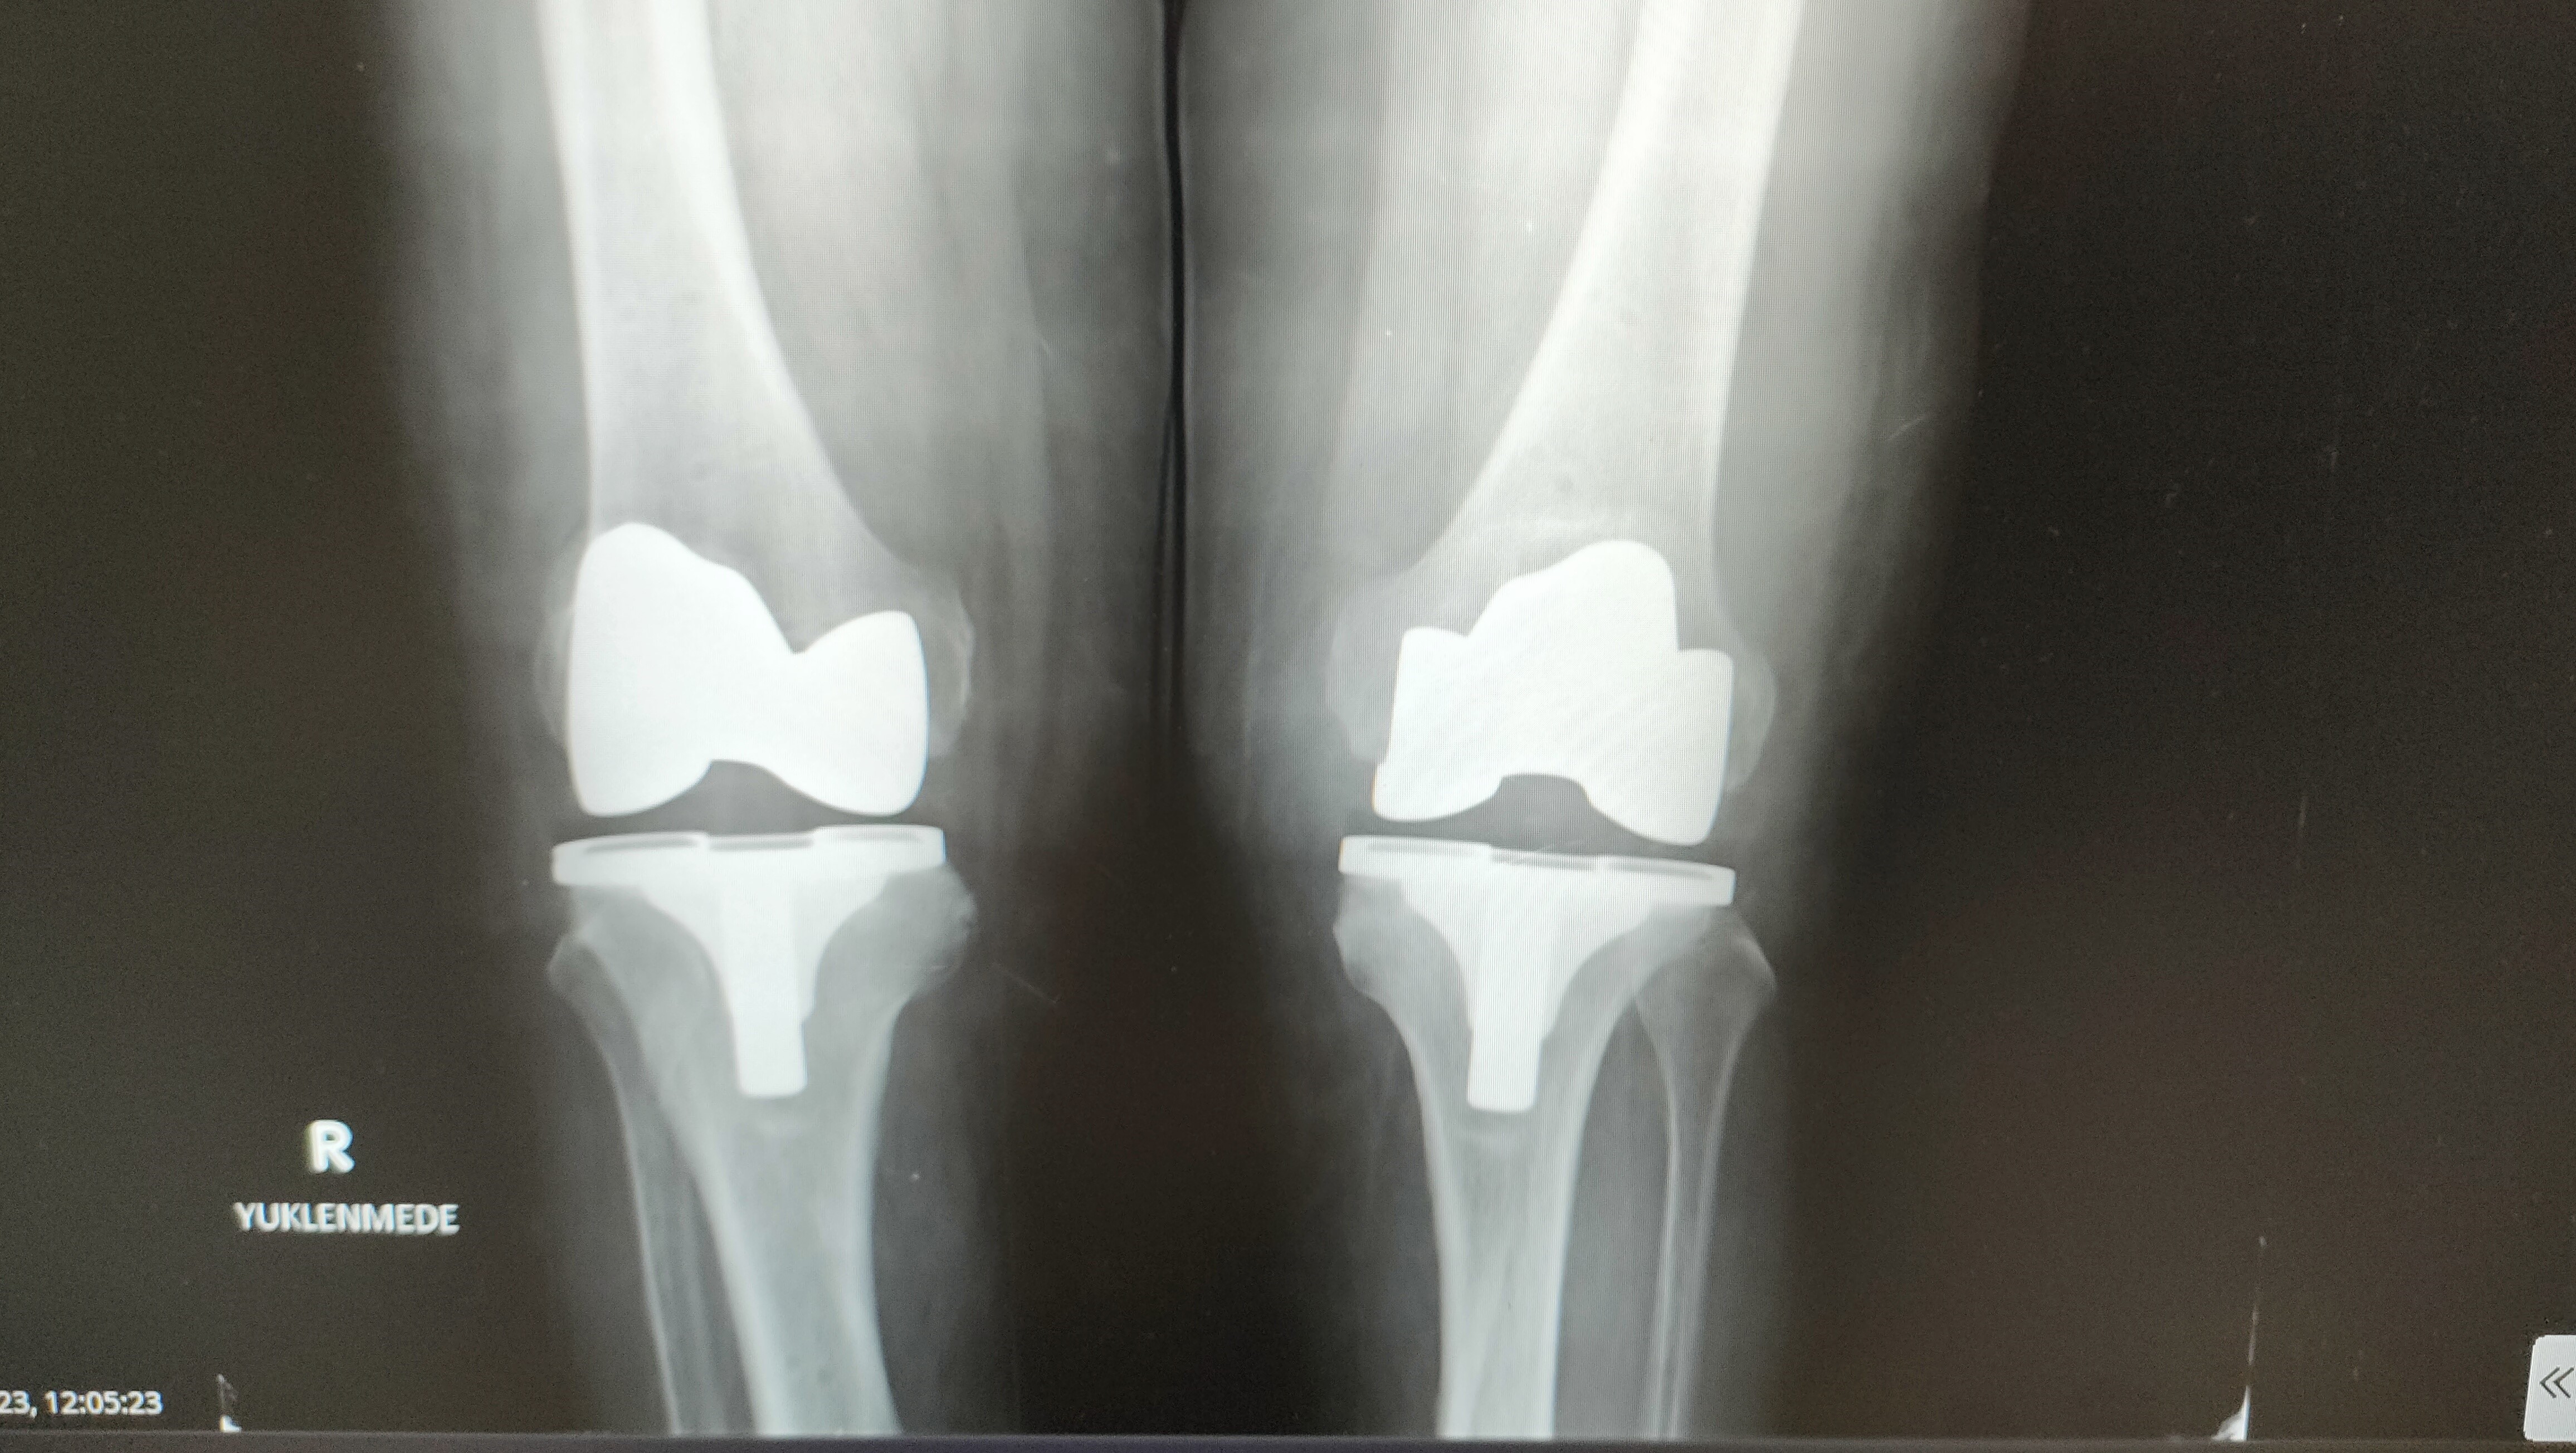

Memorial Antalya Hastanesi Ortopedi ve Travmatoloji Uzmanı Op. Dr. Murat Baloğlu, robotik diz ve kalça protezinin kullanım alanları hakkında bilgiler verdi.

"Hastaya özel üretiliyor"

Protezin ağrılı bir işlemden önce uygulandığını dile getiren Baloğlu, “Kireçlenme dediğimiz durum olunca, iki kemik birbirine sürtüyor, hasta ayağa kalktığında, hatta sonraki dönemlerde istirahatte bile ağrıdan dolayı duramıyor. Bırakın yürümeyi normal istirahat ağrısı, gece ağrısı oluyor. Dolayısıyla bu hastalar bize, ‘Beni ameliyat edin’ diye geliyor. Çoğu hasta grubumuz böyle. Robotik protezler diğer protezlere göre şöyle bir farklılığı var; biz bu protezi hastaya özel ürettiriyoruz. Ameliyat öncesinde tomografi ve filmler sisteme yükleniyor. Sistem sayesinde protezler hastaya özel üretildiği için, kişiye özel olarak gelmiş oluyor. Bu protezi robotik yardımlı olarak ameliyatta hastaya uyguluyoruz. Bu işlem kabaca yarım saat 45 dakika sürüyor” dedi.

Hastanın bir iki gün hastanede kaldıktan sonra yürür şekilde taburcu olduğunun altını çizen Baloğlu, “Bu ameliyatta daha az kesiden işlem yapıldığı hem de hastaya özel protez kullanıldığı için hata payımız neredeyse sıfır. Bu nedenle hasta da bir ay sonra geçirdiği bu işlemi neredeyse unutmuş olur.

Yürüme sıkıntısı çeken hasta rahatlıkla yürüyerek çıkıyor. Çünkü ağrı olmadığı zaman hasta zaten yürümek istiyor ve bunu biz de talep ediyoruz. Dolayısıyla bundan sonrasında, ‘aman yürüme üzerine basma’ demiyoruz. Tam yükle mobilize olur şekilde hasta gidebilir buradan. Özellikle namaz kılma noktasında zorlanan yaşlılarımızdan çok soru geliyor. Robotik protezlerin dizaynında mobil dediğimiz hareketli protezlerde namaz kılma anlamında bir engel durum yok. Biz bunu gerekli rehabilitasyon yapıldıktan sonra hasta sandalye ya da başka bir şey kullanmadan namazını kılabilir” ifadelerine yer verdi.